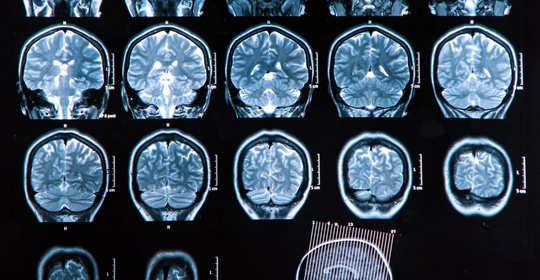

急性腦梗塞:診斷與治療